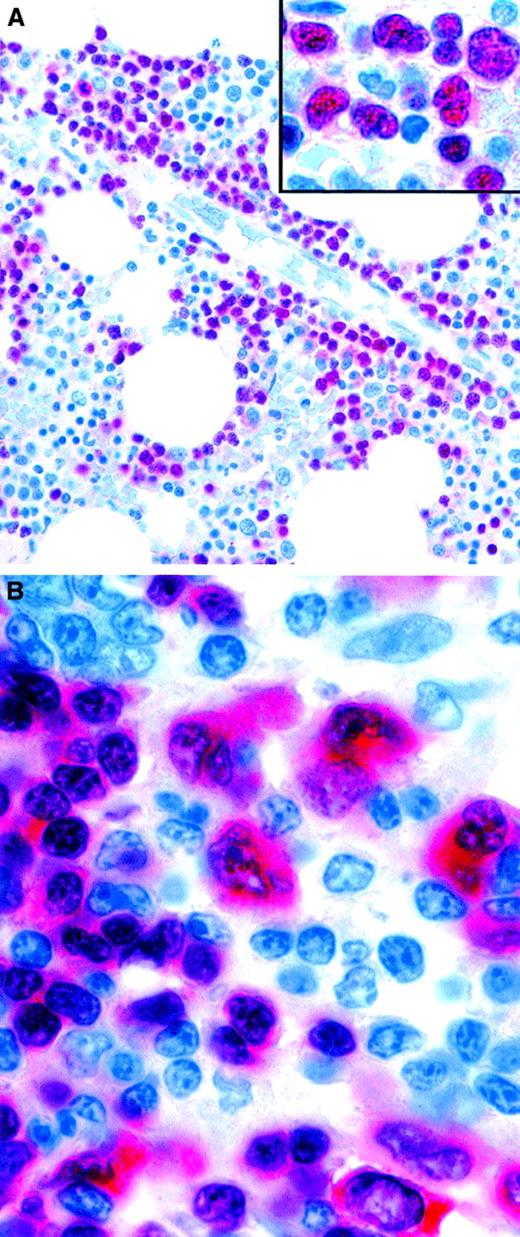

Expression of the PAX-5 (BSAP) transcription factor in neoplastic lymphoid cells.

(A) Pro-B acute lymphoblastic leukemia cells in a bone marrow biopsy specimen are selectively stained. The inset is a higher magnification, showing the irregular nuclei of PAX-5–positive leukemic cells. (B) Tumor cells of classic HD showing nuclear labeling, as well as cytoplasmic staining. Normal residual mantle zone B cells also express PAX-5 (APAAP technique in paraffin sections). Original magnification A, × 400; A inset, × 800; B, × 1000.

PAX-5 may prove to be a valuable diagnostic marker in paraffin-embedded biopsy specimens of B-lymphoblastic neoplasms because it is expressed strongly in such samples and is negative in T-cell lymphoblastic proliferations (Figure 5A; B.F., unpublished data, 2001). HD sometimes mimics ALCL, and PAX-5 may be useful in such cases because Reed-Sternberg cells are usually positive132 (Figure 5B), whereas ALCLs (both ALK positive and ALK negative) are consistently negative for PAX-5.